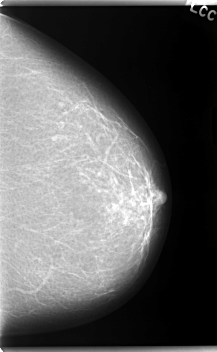

C_0057_1.RIGHT_CC

RIGHT_CC LINES 5944 PIXELS_PER_LINE 3880 BITS_PER_PIXEL 12 RESOLUTION 50 OVERLAY

FILE: C_0057_1.RIGHT_CC.OVERLAY

TOTAL_ABNORMALITIES 1

ABNORMALITY 1

LESION_TYPE CALCIFICATION TYPE PLEOMORPHIC DISTRIBUTION CLUSTERED

ASSESSMENT 4

SUBTLETY 3

PATHOLOGY MALIGNANT

TOTAL_OUTLINES 1

BOUNDARY